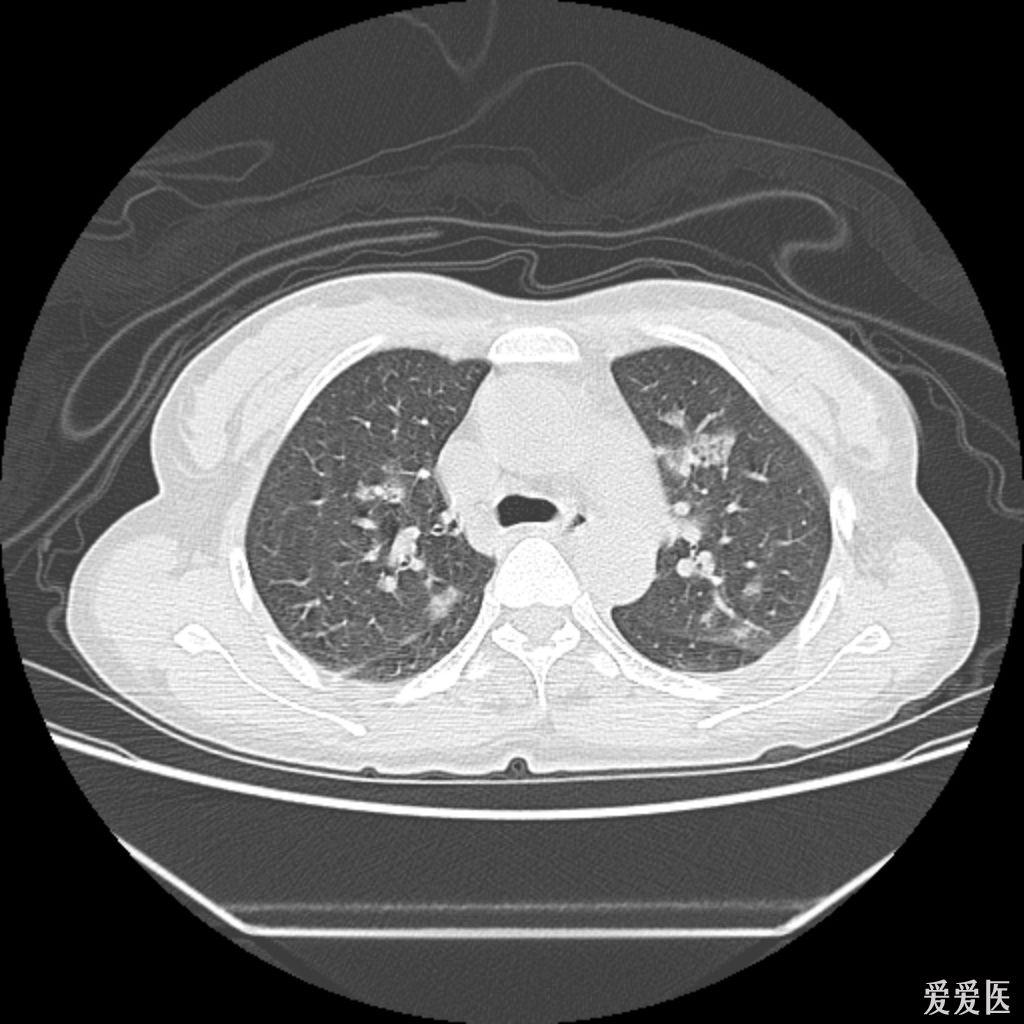

肺部真菌感染ct

图片尺寸1024x1024

ct秒杀肺真菌感染的鉴别诊断快速掌握